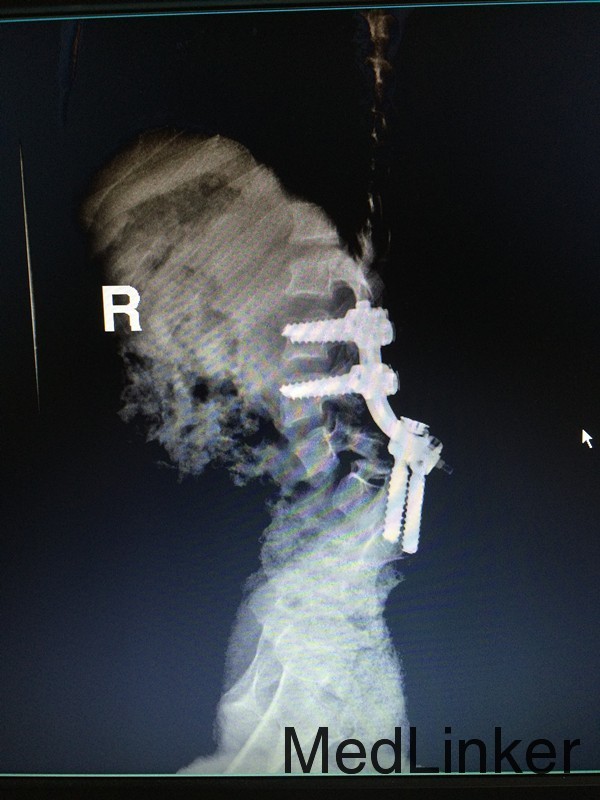

诊断:脊髓栓系综合症 治疗:神经外科联合骨科在全麻下行脊髓栓系松解、椎板修补术,术后予对症支持治疗。

随访:患者双下肢活动感觉较前稍好转。 讨论:脊髓位于脊椎管中,人在生长发育过程中,脊椎管的生长速度大于脊髓,因此脊髓下端相对于椎管下端逐渐升高。脊髓栓系即脊髓下端因各种原因受制于椎管的末端不能正常上升,使其位置低于正常。它是多种先天性发育异常导致神经症状的主要病理机制之一,由此而导致的一系列临床表现即称为脊髓栓系综合征,又称脊髓拴系综合征。